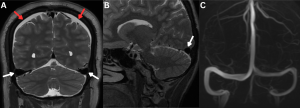

Fig 3: A 50-year-old with chronic orthostatic headaches and mild cognitive slowing.

Figures A and B: Coronal and Sagittal T2-weighted image shows prominent bilateral transverse sinuses with convex margins (white arrows) and bilateral subdural collections (red arrows).

Figure C: MR venogram confirms engorgement of the dural venous sinuses.